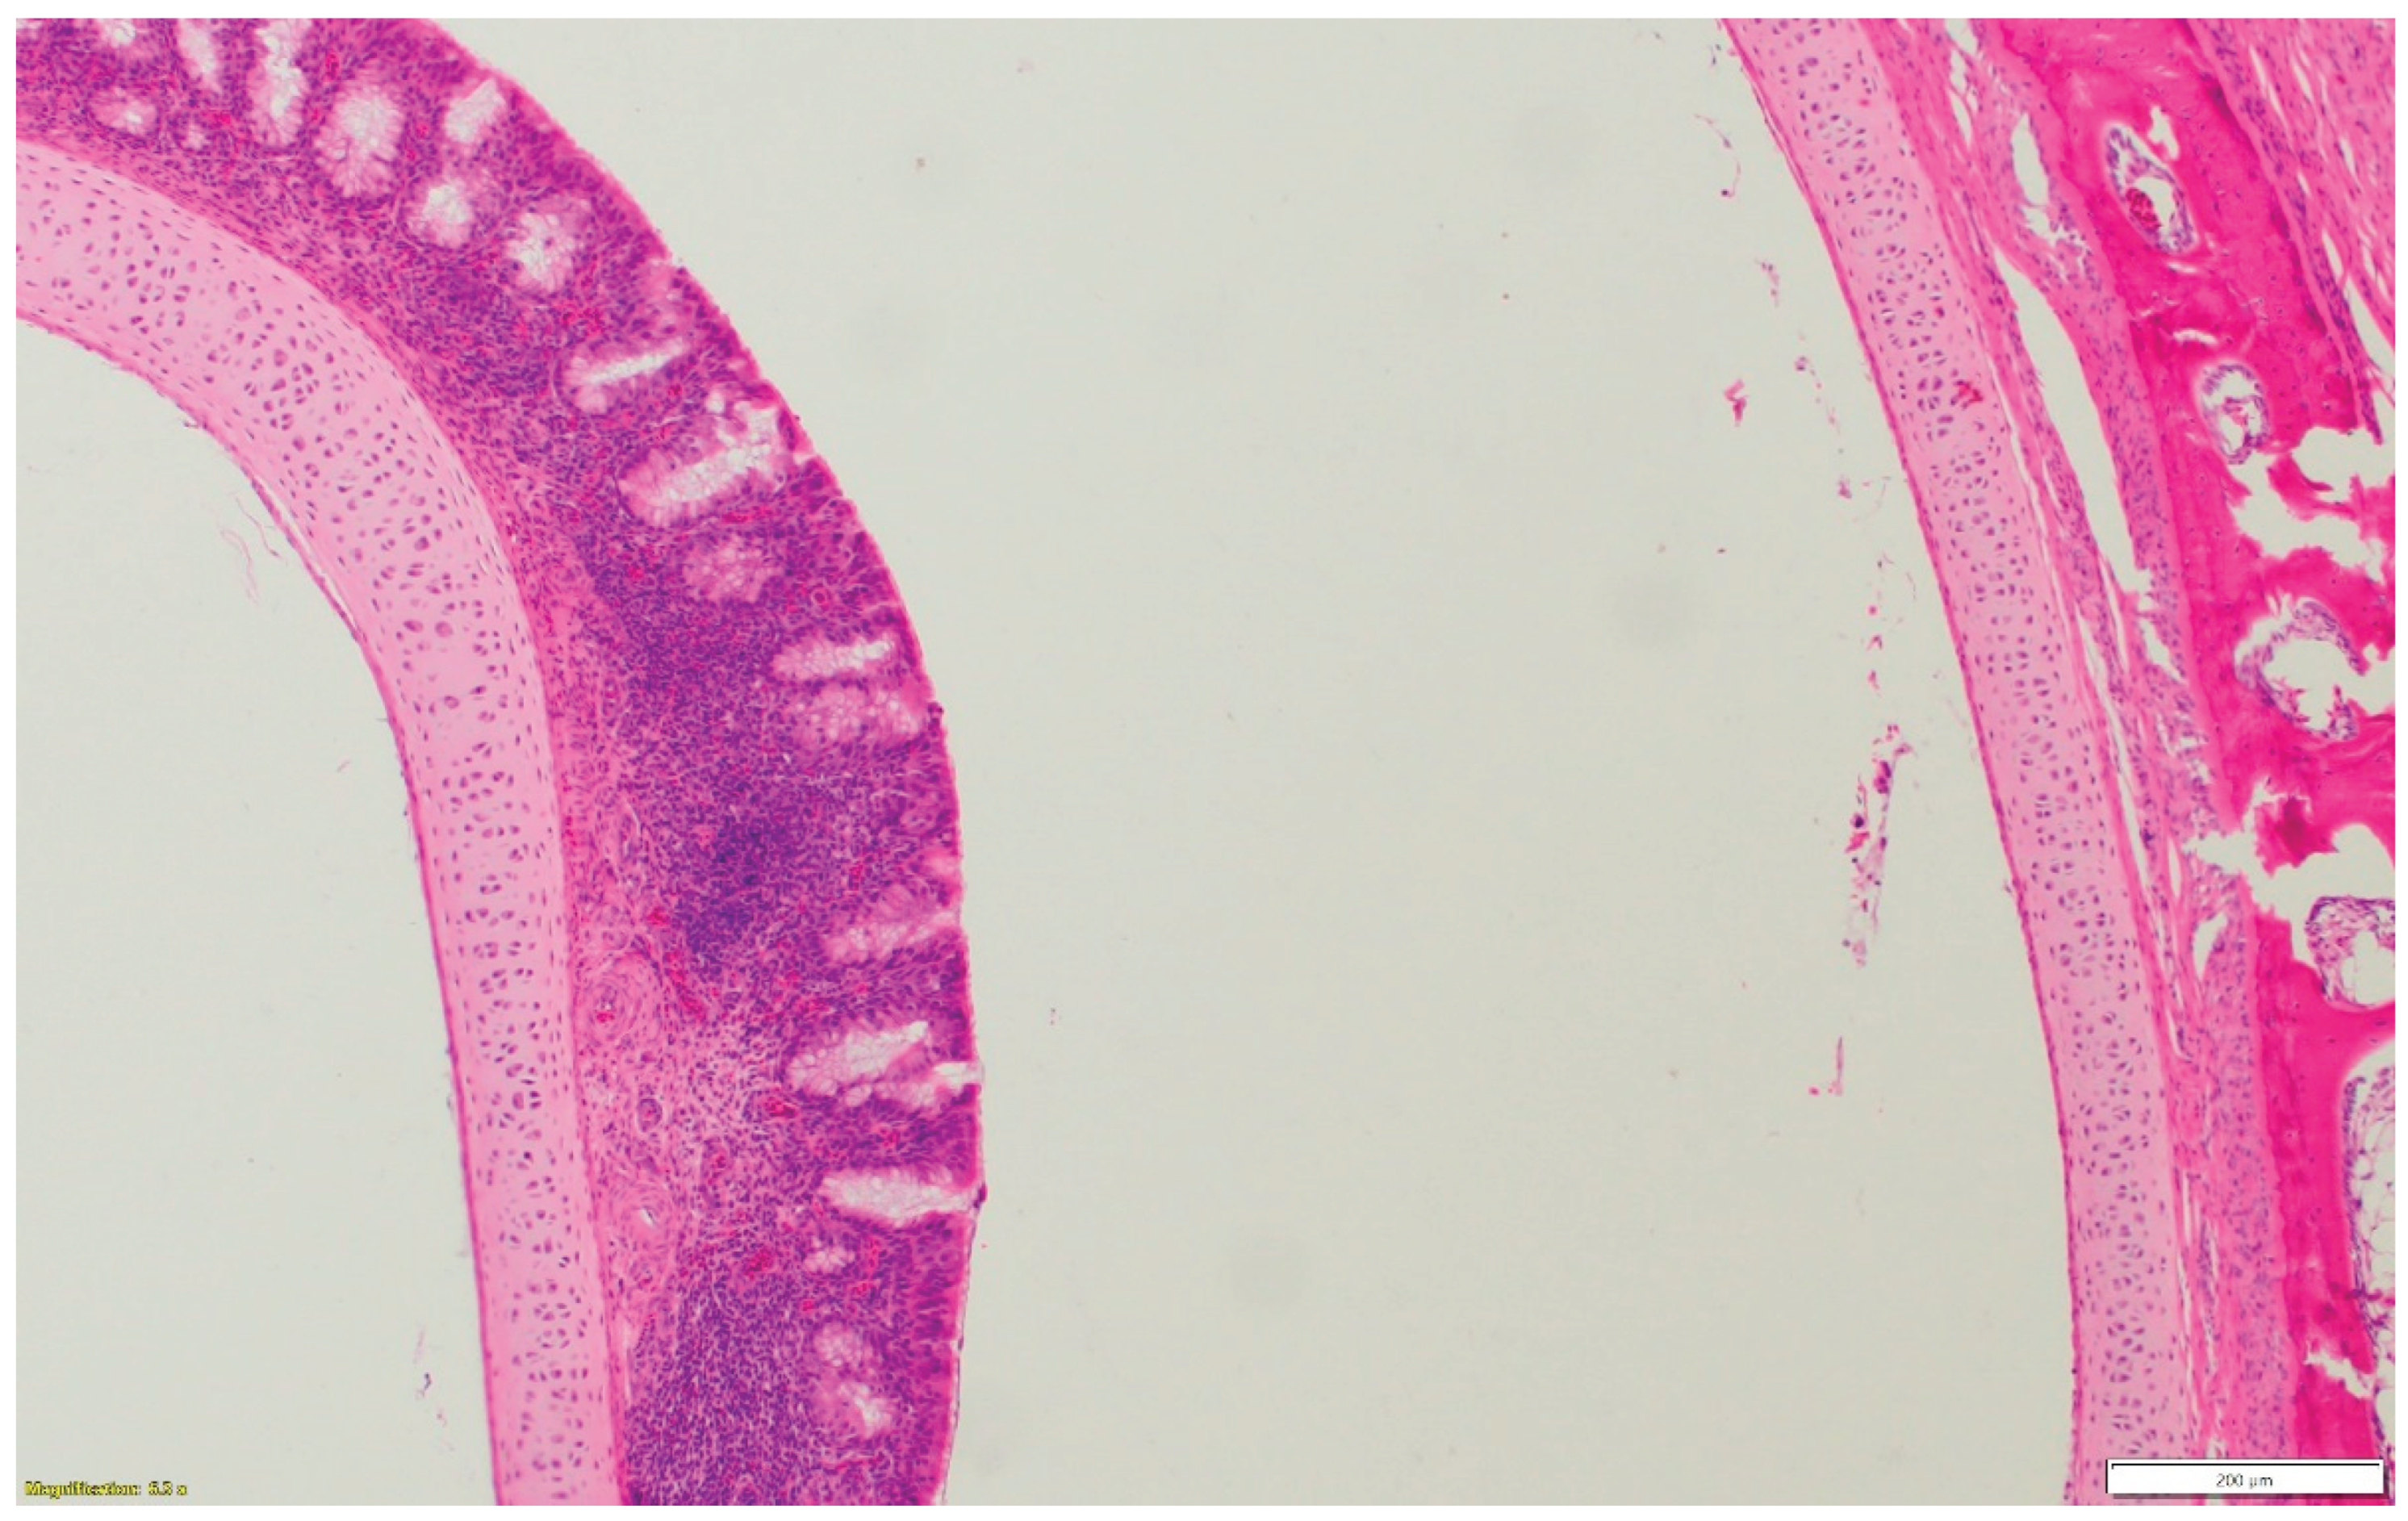

3.1. Turkeys infected with aMPV at 1-day-old (Figure 2a) had a higher total HRI compared with noninfected controls. The gap between the two groups increased significantly as the birds aged. Sinus and eyelid scores were the main contributors to the difference between the control and infected groups. A similar pattern was observed in groups inoculated at 7- and 14-day-old (Figure 2 b-c), but with higher scores. Sinus was the central part of the score difference, followed by the eyelids.

3.2. Chickens infected with aMPV at 7- and 14-day-old (Figure 3a-b): A similar pattern to the turkeys inoculated with AMPV at 7- and 14-day-old. Similarly, sinuses and eyelids created the main difference between the control and infected groups.

3.3. Turkeys inoculated with aMPV at 7 days of age showed higher lesion scores at 10 DPI compared with the non-infected control group. Sinus and eyelids were the main organs scoring points compared with other organs (Figure 4a).

3.4. Turkeys inoculated with low pathogenic avian influenza (LPAI-H4N6) at 7 days of age had also increased histologic lesion scores at 7 DPI compared with the non-infected control group. Sinus, lungs, eyelids, and trachea were orderly contributing to a higher total HRI (Figure 4b).